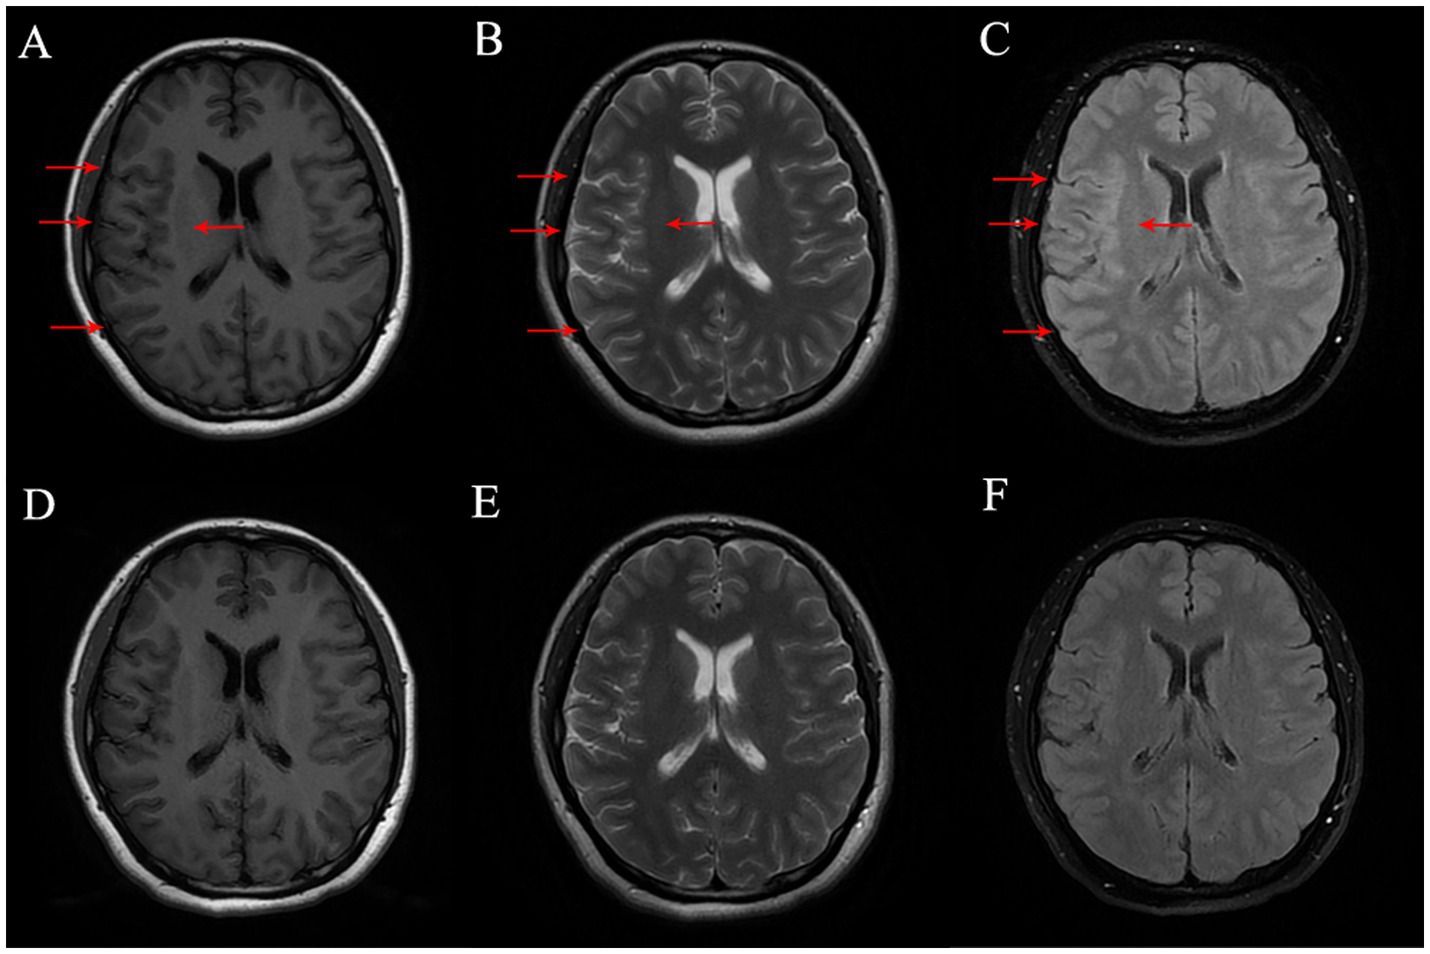

Physical examination revealed non-fluent speech, and muscle strength in the left upper limb was graded at 1. Both the Babinski sign and the Chaddock sign were negative. Brain magnetic resonance imaging (MRI) revealed hypointensity on T1-weighted images and hyperintensity on T2-weighted and fluid-attenuated inversion recovery (FLAIR) sequences in the right frontal and parietal sulci. There was slight thickening of the cortex in the right frontal, parietal, and temporal lobes. Enhanced brain MRI showed no marked enhancement (Figure 1). To assess for spinal cord involvement, a thoracic spine MRI was performed, which returned normal results. Due to the patient’s financial constraints and the absence of symptoms indicating cervical and lumbar spinal cord involvement, MRI of the cervical and lumbar spine was not conducted. Blood test results showed a leukocyte count of 14.6 × 109/L, with neutrophils accounting for 79.7%. The erythrocyte sedimentation rate (ESR) was 27 mm/h, the folic acid level was 6.07 mmol/L, the fibrinogen level was 5.65 g/L, the prothrombin time (PT) was 15 s, the triglyceride levels were 2.57 mmol/L, and the total cholesterol levels were 7.08 mmol/L. Cerebrospinal fluid (CSF) analysis revealed a slightly increased white cell count of 15 × 106/L and glucose levels of 4.9 mmol/L, with normal protein and chloride levels. MOG-IgG was detected in both CSF (titer: 1:10) and serum (titer: 1:32). Aquaporin-4 antibodies, autoimmune encephalitis antibodies, and paraneoplastic antibodies were negative in both serum and CSF. Vitamin B12, homocysteine, thyroid hormones, related antibodies, and tumor markers were within normal limits. Additional autoimmune, infectious, and metabolic evaluations yielded negative results.

Figure 1. (A–C) Brain MR on Tl FLAIR image, T2-weighted image and T2 FLAIR image before treatment, respectively, and the lesion was marked with red arrow. (D–F) Brain MR on Tl FLAIR image, T2-weighted image and T2 FLAIR Image six-month after treatment, respectively.